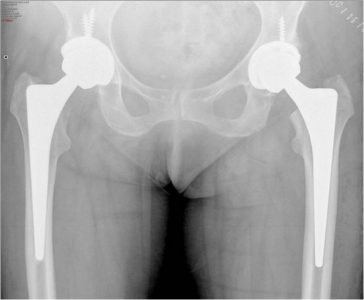

Στην ολική αρθροπλαστική ισχίου αντικαθιστούμε τις κατεστραμμένες αρθρικές επιφάνειες με μεταλλικές προθέσεις τιτανίου, που επιτρέπουν πλήρεις και ανώδυνες κινήσεις της άρθρωσης. Η εφαρμογή των πλέον σύγχρονων μεθόδων μικρής παρεμβατικότητας (MIS) και αποθεραπείας εγγυάται τα καλύτερα δυνατά αποτελέσματα με την άμεση μετεγχειρητική κινητοποίηση, την ολιγοήμερη παραμονή στην κλινική και την ταχύτερη επαναφορά του ασθενούς στις επιθυμητές καθημερινές του δραστηριότητες.

Είναι τεχνική ολικής αρθροπλαστικής μικρής παρεμβατικότητας (Minimally Invasive Surgery). Χαρακτηρίζεται όχι απλά από την μικρότερη τομή του δέρματος, αλλά και την μικρότερη δυνατή διατομή των υποκείμενων ιστών και μυών. Αυτό έχει ως αποτέλεσμα την αποφυγή μυικών βλαβών, την μικρότερη διάρκεια του χειρουργείου (λιγότερο από 1 ώρα), την αποφυγή μετάγγισης αίματος (στην πλειοψηφία των ασθενών), την διατήρηση των επιπλοκών στο χαμηλότερο επίπεδο και την γρηγορότερη κινητοποίηση και αποκατάσταση του ασθενούς. Σε συνδυασμό με τις προθέσεις τιτανίου, επιτυγχάνεται βιωσιμότητα της νέας άρθρωσης πάνω από 20-25 χρόνια στο 95% των περιστατικών.